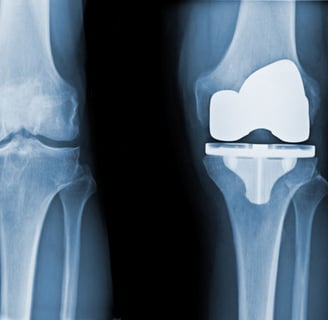

A Total Knee Replacement (TKR) is a surgical procedure where the entire knee joint surface is replaced with artificial components made of metal and plastic. It's done to relieve severe pain and stiffness, usually caused by arthritis, injury, or other joint problems that haven’t responded to other treatments.

• The worn-out cartilage and a small amount of underlying bone are removed from the thighbone (femur), shinbone (tibia), and sometimes kneecap (patella).

• These surfaces are then replaced with metal implants, and a smooth plastic spacer is inserted between them to allow smooth movement.

• The kneecap may also be resurfaced with a plastic button depending on the case.